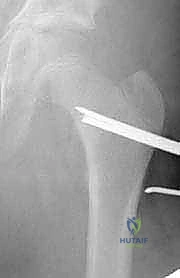

6. إدخال الشريحة والتثبيت (Plate Insertion & Fixation)

يتم إدخال نصل الشريحة ذات الزاوية 90 درجة في المسار الذي تم تحضيره في عنق الفخذ. ثم يتم ضم جزئي العظم المقطوعين معاً (إغلاق الفجوة)، مما يؤدي فوراً إلى تغيير زاوية عنق الفخذ إلى الوضع الطبيعي الجديد. يتم تثبيت الجزء الطويل من الشريحة على جسم عظم الفخذ باستخدام براغي قوية من التيتانيوم أو الفولاذ الطبي المقاوم للصدأ.

7. الإغلاق التجميلي

بعد التأكد من صلابة التثبيت ووضعية المفصل المثالية عبر الأشعة، يتم غسل الجرح وإغلاقه بطبقات متعددة باستخدام خيوط تجميلية لتقليل الندبات.

لماذا الشريحة ذات الزاوية 90 درجة (90-Degree Blade Plate) تحديداً؟

قد يتساءل البعض: لماذا يصر الأستاذ الدكتور محمد هطيف على استخدام هذا النوع المحدد من الشرائح في عمليات قطع عظم الفخذ الداني التقويمي؟ الإجابة تكمن في الميكانيكا الهندسية:

- التثبيت فائق الصلابة (Rigid Fixation): النصل العريض للشريحة الذي يدخل في عنق الفخذ يوفر ثباتاً دورانياً وزاوياً لا مثيل له، مما يمنع العظمة من التحرك أثناء فترة الالتئام.

- التحكم الدقيق في الزوايا ثلاثية الأبعاد: تسمح هذه الشريحة بتصحيح زاوية الميل (Varus)، وكذلك تصحيح الدوران الخاطئ للعظمة (Derotation) في نفس الوقت.